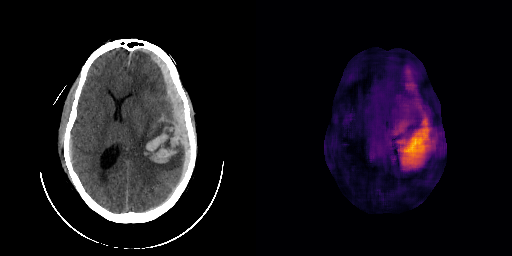

fig:qualitative_ich

ICH

healthy

We show some slices with examples of ICH in \figurereffig:qualitative_ich as well as surface renderings of scans of subjects with cranial fractures in \figurereffig:qualitative_fractures. (As a reference we also included the same examples for the AE in Appendix D in \figurereffig:qualitative_ich_ae.) It is noticeable that the reconstruction error is high where there is an anomaly. The reconstruction error generally seems to continuously depend on the amount of the patch that is anomalous, as the error maps generally seem to be rather smooth.

The performance for the models used for \figurereffig:qualitative_ich and LABEL:fig:qualitative_fractures are shown in \figurereffig:roc_performance. We observe see that the detection of fractures is the more challenging task for our method than the detection of ICH. This might be due to the smaller number of scans available to evaluate it on (see Appendix B). To put these results in context we provided a table with the inter rater agreement on these tasks in Appendix B: The performance in terms of AUROC is around lower than the average raters.